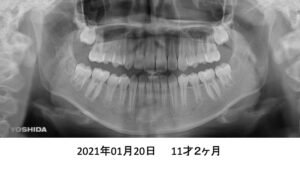

もう1症例、8才4ヶ月の患者さんです。

パノラマでは、永久歯が入るスペースが足りないように見えます。

4年後です。治療は何もしていません。

さらに2年後、全ての歯がちゃんと萌出しました。